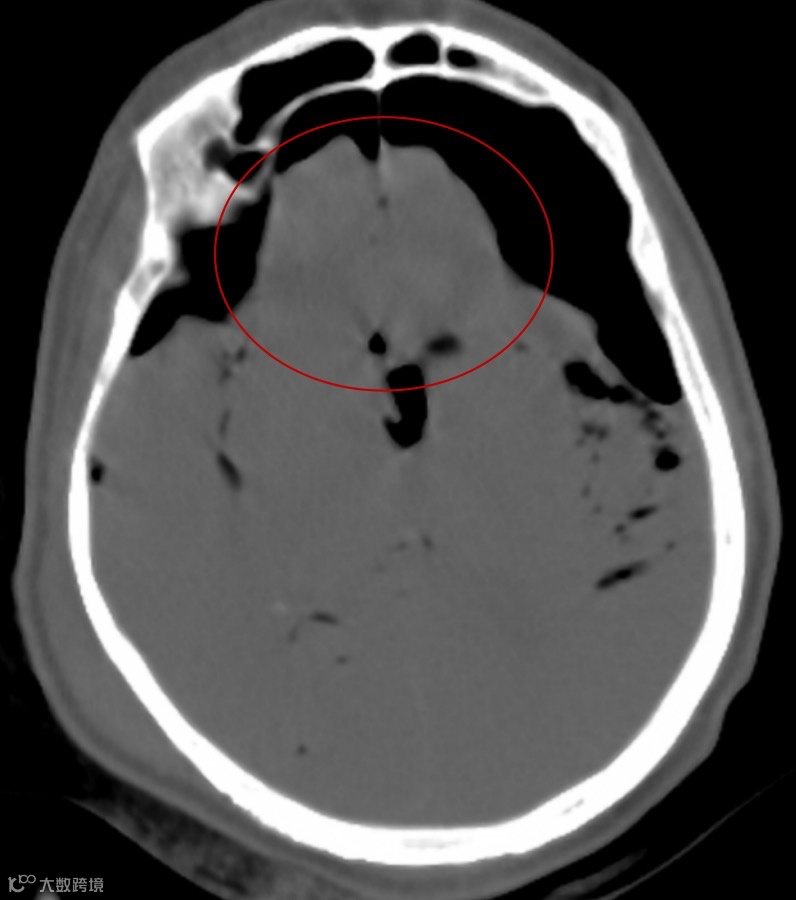

张力性气颅初始,高张力的气体可压迫邻近脑组织(通常见于额叶),额叶被推到一起、变尖及移位,在中线处形成山峰样改变,即山峰征,周围是空气。

随着病情的发展,颅内气体增多,额叶开始分离,坍塌的额叶和额极大脑半球间的裂隙增宽而出现富士山样的轮廓,称为富士山征。

富士山征(箭头)

额极之间(纵裂池)的空气表明空气压力至少大于额叶之间脑脊液的表面张力。